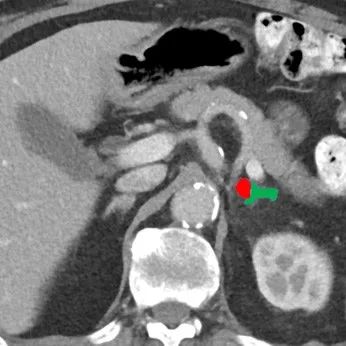

肾上腺腺瘤微波消融术后一个月影像复查

术后肾上腺CT增强检查:左侧肾上腺腺瘤完全灭活、无强化(红色区域);正常肾上腺外侧肢保存,可见强化表现(绿色区域)。

图8. 左侧肾上腺。

图9. 肾上腺腺瘤无强化(红色)。

图10. 肾上腺外侧肢保存(绿色)。